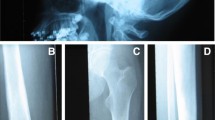

Pycnodystostosis (OMIM 265800), meaning dense defective bone, is a rare, autosomal recessive osteochondrodysplasia. The first case was described in 1923 but the features of the disease were defined by Maroteux and Lamy in 1962 [8, 9]. The prevalence of pycnodysostosis is estimated to be 1–1.7 per million, it is equally distributed between women and men and about 200 cases have been reported in the literature [10]. The disease is characterized by osteosclerosis, short stature, acro-osteolysis of the distal phalanges, clavicular dysplasia, skull deformities with delayed suture closure, and bone fragility (Fig. 1a, b). The most commonly described phenotype of pycnodystostosis is short stature with increased bone mineral density and increased bone fragility. In infants, open fontanels and sutures with frontal and parietal bossing and hypoplasia of the maxilla and mandible with an obtuse mandibular angle are frequently seen. Dentogenesis with delayed eruption of the teeth may also be present.

Pycnodysostosis: a Open sutures; b Acro-osteolysis; c Iliac crest bone biopsy showing cortical (Ct) and trabecular osteosclerosis (from [11]); d High magnification of an iliac crest bone biopsy showing an osteoclast adjacent to a resorption lacuna filled with unmineralized matrix (from [12]); SEM images of odanacatib-treated osteoclast culture on dentine slides: e Control, showing a deep resorption pit; f Treated, showing discrete, small, shallow resorption pits (from [87])

Sclerosteosis: a Enlarged skull and mandible with facial palsy; b Syndactyly; c Biopsy of compact bone with high numbers of osteoblasts and osteoid van Buchem disease: d Typical features with facial palsy; e Petrous part of temporal bone and acoustic meatus (arrows) of a normal skull (upper) and of a skull of a patient (lower); note the increased thickening and the narrowing of the meatus (from [88]); f Increased bone formation in a biopsy from compact bone